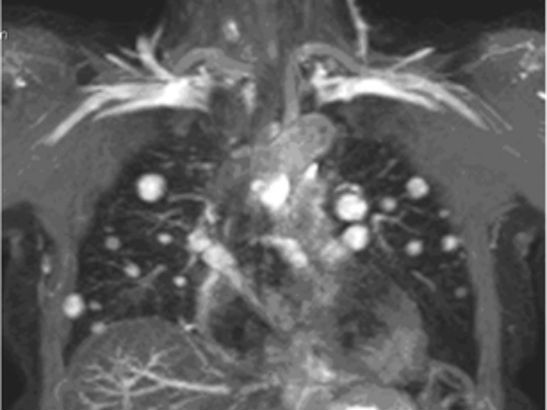

Mapping the evolutionary road to metastasis

New research into advanced prostate cancer reveals that the evolutionary path to cancer spread isn’t just a one-way street.